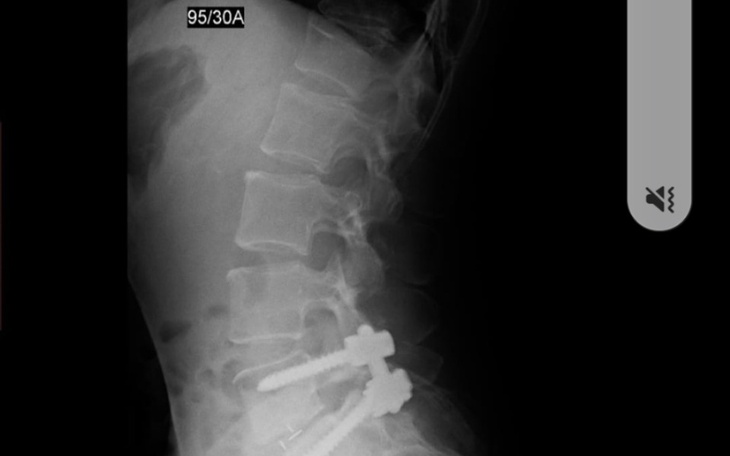

Dzień dobry jestem Małgosia mam 49 lat i jestem osobą skrzywdzona przez los. Poszukuje osób dobrego serca jestem ofiarą przemocy w rodzinie i jestem w bardzo trudnej sytuacji finansowej. Potrzebne sa środki finansowe na kolejną operacje i rehabilitację. Jestem chora na przewlekłą chorobę - Stwardnienie Rozsiane. Na tę chwile leczenie w Polsce nie jest skuteczne. Jestem po bardzo ciężkiej operacji kręgosłupa-stabilizacja tytanowa z odbarczeniem części lędziowej, gdyż podczas operacji okazało się że jeden kręg jest cały rozsypany. W obecnej chwili jest znaczne pogorszenie stanu kręgosłupa i oczekuje na kolejną operacje jeśli w Polsce znajdą się lekarze którzy podejmą się takiej operacji.